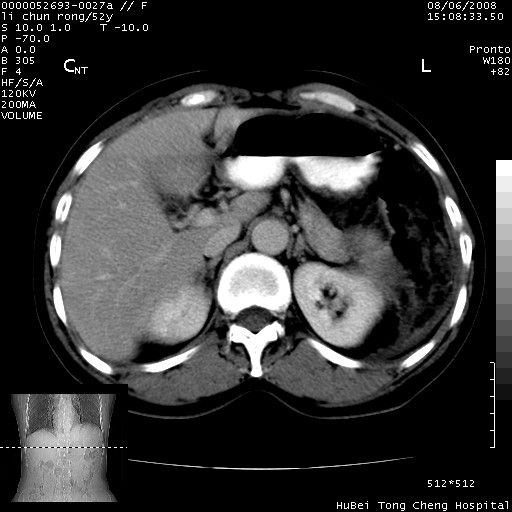

以下是引用云翔在2008-8-7 6:20:00的发言:[br]胰尾部囊性病变,考虑假囊肿,结合实验室检查疾病史

以下是引用zjzjr在2008-8-7 8:38:00的发言:[br]支持胰腺炎伴假囊肿形成,左肾小囊肿.少量腹水.

以下是引用随光逐影在2008-8-7 9:12:00的发言:[br]1)考虑胰腺炎伴假性囊肿形成可能性大;胰腺囊腺瘤待排。2)左肾小囊肿。3)少量腹水。